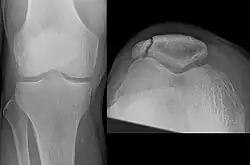

The patella can break in various ways depending on the way it is injured, and into two or more pieces.[1] Types include transverse, with one fracture line and is the most common type,[5] marginal, osteochondral and the rare vertical type, or stellate, where a direct compression force gives rise to a comminuted pattern.[5][7] Patella fractures can be further classified as displaced, where the broken ends of bone do not line up correctly and separate by more than 2mm, or undisplaced and stable where pieces of bone remain in contact with each other.[1][7] If fragments of patella bone stick out from the skin it is known as an open patella fracture, and closed if the overlying skin is intact.[1]

Transverse fracture of patella -

Comminuted fracture of patella -

Osteochondral fracture of patella -

Vertical patella fracture